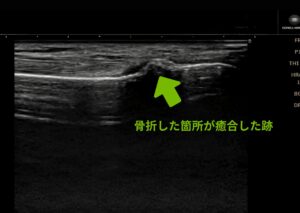

2ヶ月前にコーレス骨折(橈骨遠位端骨折)を経験し、医療機関で「骨はきれいにくっついていますね」と診断を受けた後も続く不調。

一般的な医療機関では、レントゲンで骨の状態を確認します。しかし、痛みや痺れの正体は、骨そのものではなく、その周辺の**「軟部組織(筋肉・神経・腱)」**に隠れていることが多いのです。

今回の症例では、折れたのは手首の「背側(甲側)」でしたが、実際に痛みが出ていたのは「掌側(手のひら側)」でした。

当院で**エコー(超音波画像観察装置)**を用いて詳しく観察したところ、手根管(神経の通り道)全体に強い腫れが確認できました。